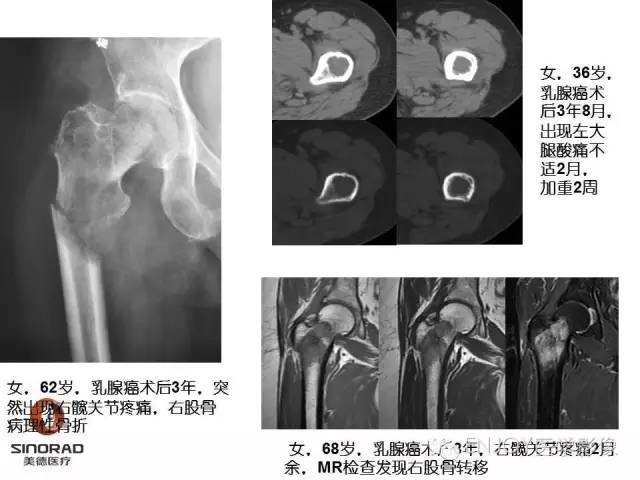

1、病灶的定性诊断是?(单选)

A:良性肿瘤

B:恶性肿瘤

C:非肿瘤

2、你的诊断(单选)

骨肉瘤(传统型)

骨肉瘤(毛细血管扩张型)

多形性肉瘤(以往称为:恶性纤维组织细胞瘤)

软骨肉瘤(2-3级)

转移瘤